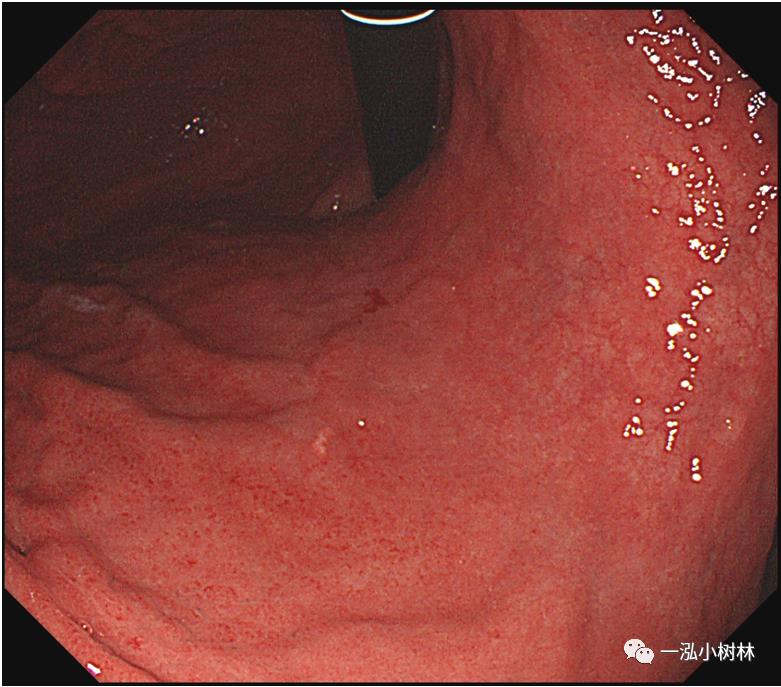

例3 胃体下部病变

图3 白光内镜:胃体下部炎症。